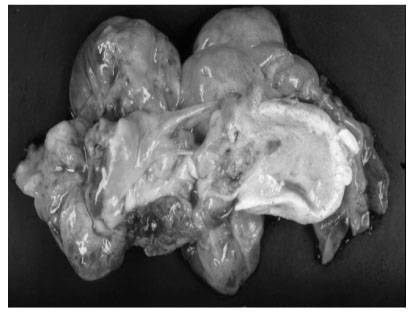

Fig 1). An explorative laparotomy revealed a 9 × 8 cm, globular encapsulated mass, located between the greater omentum and transverse mesocolon, and a 1 cm, ovoid nodule in segment IV of the liver. The mass showed no evidence of invasion of adjacent organs. Both ovaries were normal at the time of surgery. The mass was completely excised surgically, and the hepatic lesion underwent wedge resection. Grossly, the tumor was a 10 × 9 cm, whitish to gray, globular solid mass (

Fig. 2Gross appearance of the resected tumor. The tumor appears as a whitish to gray globular solid mass, measuring 10 × 9 cm. The cut surface shows semisolid grayish material and cartilaginous tissue.